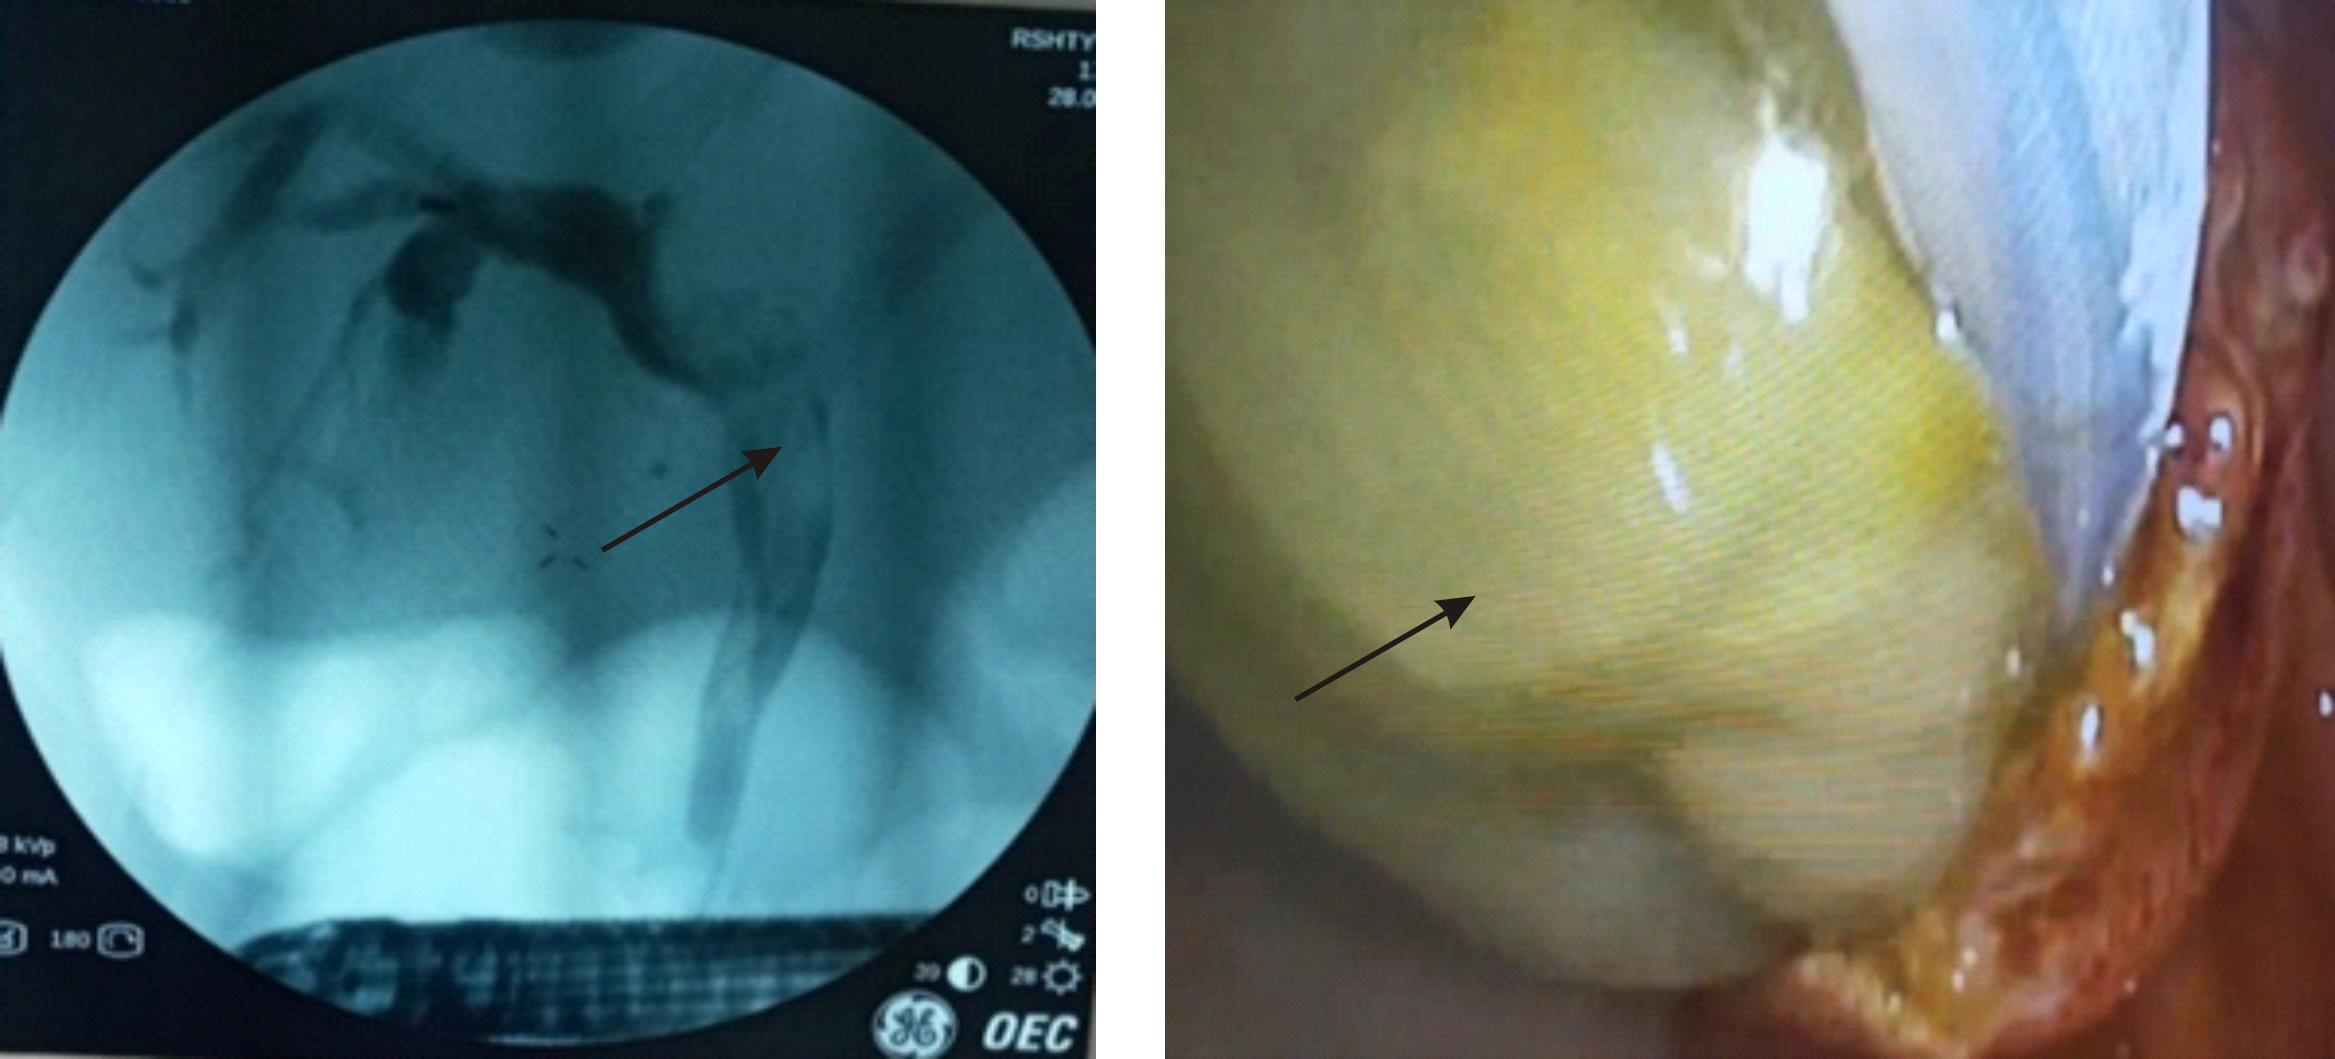

13.02.2024 больному была проведена эндоскопическая ретроградная панкреатохолангиография (ЭРПХГ) с целью констатации диагноза и декомпрессии желчных протоков. Эндоскопическим методом осуществлена папиллосфинктеротомия, при помощи специального катетера произведена канюляция общего желчного протока, после чего введено контрастное вещество для проведения холангиографии (рис. 1).

На изображении монитора рентгенотелевизионной установки обнаружено расширение общего желчного протока до 25 мм с содержимым в просвете гиперэхонных участков в средних и дистальных отделах. С использованием специальных инструментов, корзинки и баллона, из общего желчного протока осуществлено удаление гидатидного песка, фрагментов оболочек и элементов кисты. Желчные протоки тщательно промыты физиологическим раствором и гермицидами с целью максимального удаления фрагментов и содержимого эхинококковой кисты, а также профилактики развития и прогрессирования холангита. Затем через папилосфиктеротомную рану для орошения установлен катетер в общий желчный проток для введения необходимых противомикробных средств.

Рис. 1. ЭРПХГ и интрадуоденальная картина желчных ходов после папиллотомии с выделением хитиновой оболочки